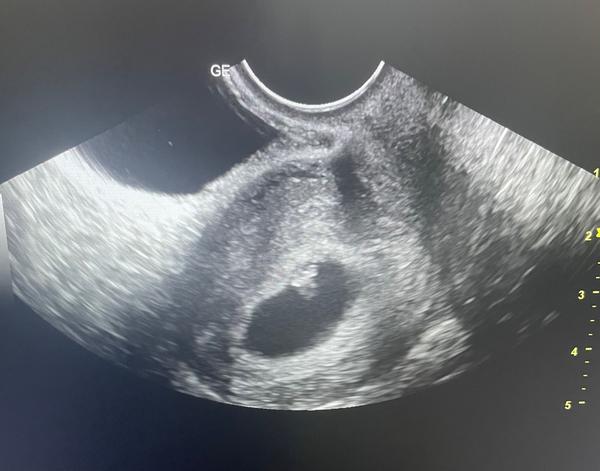

Jednovaječné dvojčatá - tlkot srdca

Ahojte, kedy ste pri jednovajecnych dvojickach poculi obe srdiecka?Hned v 6 tt? Mozu sa aj prekryvat?dakujem

Velmi to zalezi od ulozenia dvojek. V 8tt bolo pocut o vidiet obe u mna. U svagrinej bolo do 32tt vidiet iba jedno, druhe zistili az v tom tyzdni, kedze to jedno dvojca bolo poskryvane pod druhym🙃